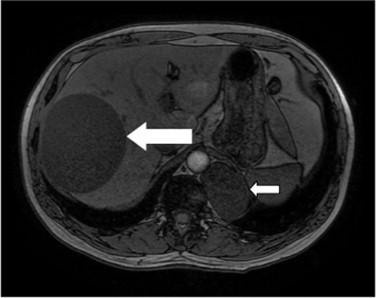

We report a case of synchronous CE of the liver and posterior mediastinum treated sequentially using chemotherapy, percutaneous aspiration with injection of a scolicidal agent and re-aspiration (PAIR) and then staged minimally-invasive surgeries.

我们报告一例肝脏和后纵隔同步发生CE的病例,该病例先后接受了化疗、经皮穿刺抽吸并注入杀头节剂及再次抽吸(PAIR)治疗,随后进行了分期微创手术。